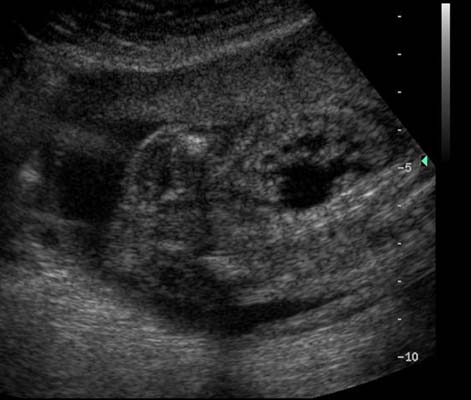

Degré variable